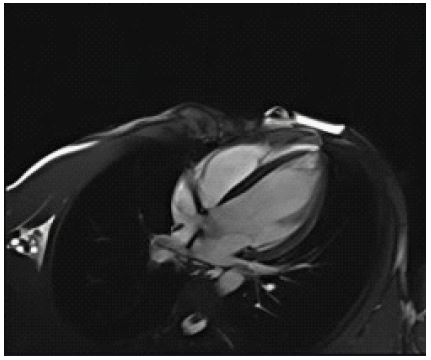

A 33-year-old female with no prior comorbidities presented with a seven-day history of high-grade fever, chills, rigors, dyspnea, and cough with borderline blood pressure requiring inotropes. Preliminary evaluation with ECG revealed sinus tachycardia and a 2D echo revealed global LV hypokinesia and severe Left ventricular dysfunction with LVEF of 30%. Initial laboratory investigations revealed elevated troponin with elevated NT-Pro-BNP suggestive of myocardial injury and acute heart failure, anemia (Hb: 9 g/dL), and elevated TSH (7.8 mIU/L), and mild renal dysfunction. The patient was admitted to the Intensive Care Unit and was treated for Heart Failure. A cardiac MRI was done, and it showed significant mid-myocardial Late Gadolinium Enhancement (LGE) in the LV free wall, sparing the endocardium and epicardium. While mid-myocardial LGE is commonly associated with myocarditis, it can also be seen in other conditions such as sarcoidosis, dilated cardiomyopathy, and Anderson Fabry disease. In this case, the findings were interpreted in conjunction with the clinical presentation, including recent febrile illness, elevated troponin, and rapid LV dysfunction. The imaging met the revised Lake Louise Criteria, supporting a diagnosis of probable myocarditis (Figures 1-3). Patient was started on IV Methylprednisolone 1 g daily for three days and then started on Oral prednisolone 1 mg/kg/day. Four days into her illness, she experienced two syncopal episodes and was found to have bradycardia with a heart rate of 30/min. An ECG revealed a complete heart block (Figure 4) with a wide-complex escape rhythm, and rising troponin levels indicated myocardial injury. A transvenous temporary pacemaker was placed, stabilizing her initially. A formal Transthoracic Echocardiogram (TTE) was performed after temporary pacemaker placement, which revealed the same moderate to severe LV dysfunction and no additional complications. Sarcoidosis was considered due to mildly elevated ACE levels (61 U/L), but further testing, including CT chest, EBUS, and node biopsy, was not feasible due to the patient’s rapid deterioration. Giant cell myocarditis, though rare in young patients, was also considered, given the aggressive course and refractory ventricular arrhythmias. A comprehensive evaluation could not be conducted due to the rapid progression of the disease. However, viral myocarditis remained the most likely etiology based on clinical presentation, negative H1N1 swab, and absence of autoimmune markers (ANA: 1:40, dsDNA < 30 IU/mL) (Table 1). After TPI, she developed slow ventricular tachycardia (130/min) (Figure 5), which persisted despite multiple attempts at overdrive pacing. Amiodarone was initiated (150 mg IV bolus, followed by 1 mg/min for 6 hours, then 0.5 mg/min for 18 hours), but VT remained refractory. Lidocaine (1.5 mg/kg IV bolus, followed by 1 mg/min infusion) was added, but the arrhythmia remained refractory. Overdrive pacing was attempted but was discontinued after the onset of Polymorphic Ventricular Tachycardia (PMVT). Given the fulminant nature of myocarditis, catheter ablation was not attempted, as the arrhythmogenic substrate was likely diffuse rather than focal, reducing the likelihood of procedural success. The patient continued to deteriorate into refractory cardiogenic shock despite maximal inotropic and antiarrhythmic therapy. She experienced cardiac arrest and could not be resuscitated. Referral for mechanical circulatory support (ECMO) was considered, but stabilization for transfer was not possible given the rapid decline. Post-mortem biopsy was not performed due to lack of consent.